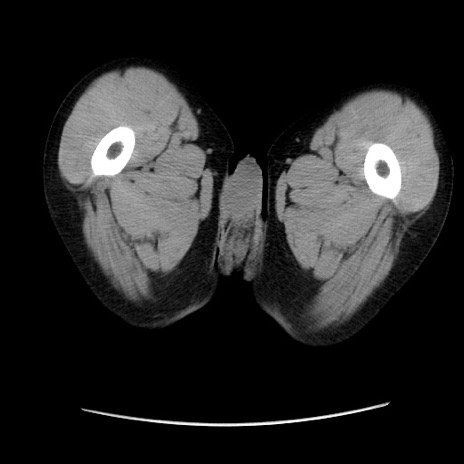

冠状断像